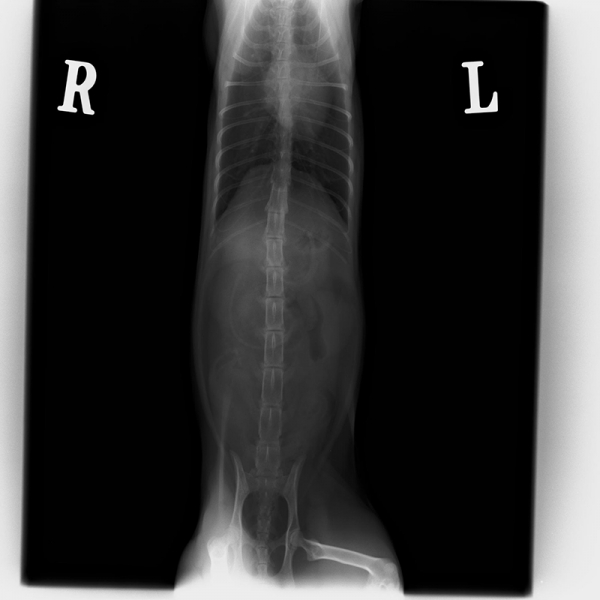

| ケース | 18歳、去勢済男の子のネコちゃん |

| 症状 | 食欲不振と嘔吐で来院されました。血液検査を行ったところ、腎臓の数値の増加が認められました。レントゲン検査ならびにエコー検査において右尿管結石による尿管閉塞が疑われました。 |

| 手術方法 | 尿管閉塞が認められた場合、1,尿管切開による結石摘出術 2,尿管の一部を切除し膀胱と吻合する尿管膀胱吻合術 3、人工尿管を用いた腎臓皮下尿管バイパス手術 4,尿管ステント挿入 5,一時的な腎瘻チューブ設置術などがあります。それぞれの手術方法には一長一短があります。今回はまだ年齢も若く飼い主様のご意向により、尿管切開による結石の摘出を行いました。 |

| 術後経過 | 術後、水腎は解消し腎臓の数値も低下し順調に排尿が認められました。 |

| 図1 | 図2 | 図3 |